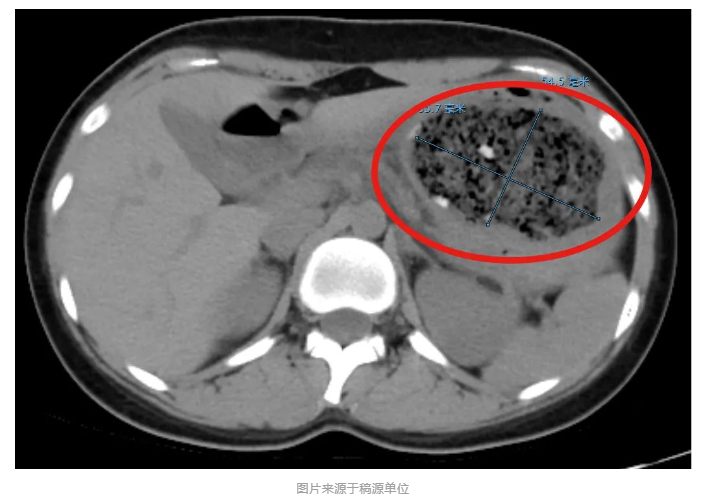

接诊的消化内科副主任杨晶简单问了病史后,给倩倩安排了腹部CT平扫检查,结果发现一个8.6cm×5.5cm左右的巨大的异物把她的胃塞得满满当当!

在进一步胃镜检查后,杨晶发现,倩倩胃里面的结石体积庞大,几乎不留什么空隙,这使得常规的异物圈套器无法施展。